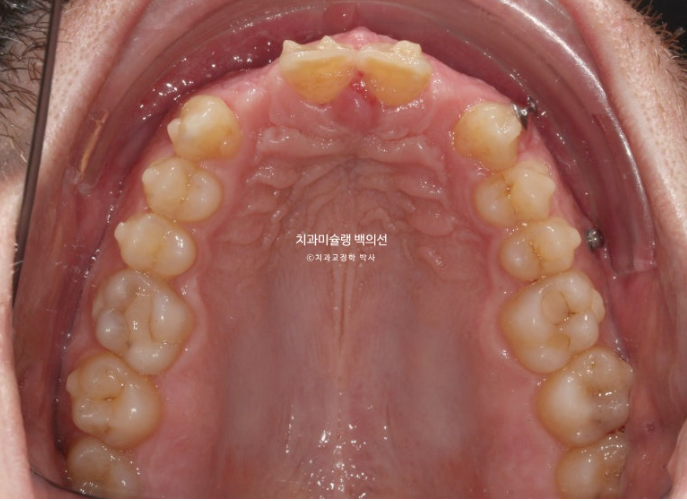

25.04

임플란트는 먼저 뿌리를 심고 몇달간 안정화 기간을 거쳐서 치아머리를 만듭니다.

약 6개월간 안정기간을 충분히 가진 후 25년 4월 임플란트 머리를 올립니다.

25.05

6개월의 기다리는 기간동안 환자분이 유지장치를 소홀히 끼셨는지 세워놨던 앞니 뿌리가 다시 약간 기울어졌죠

이 부분 개선을 위해 앞니 4개에 부분교저용 mta 장치를 붙이기로 했습니다.